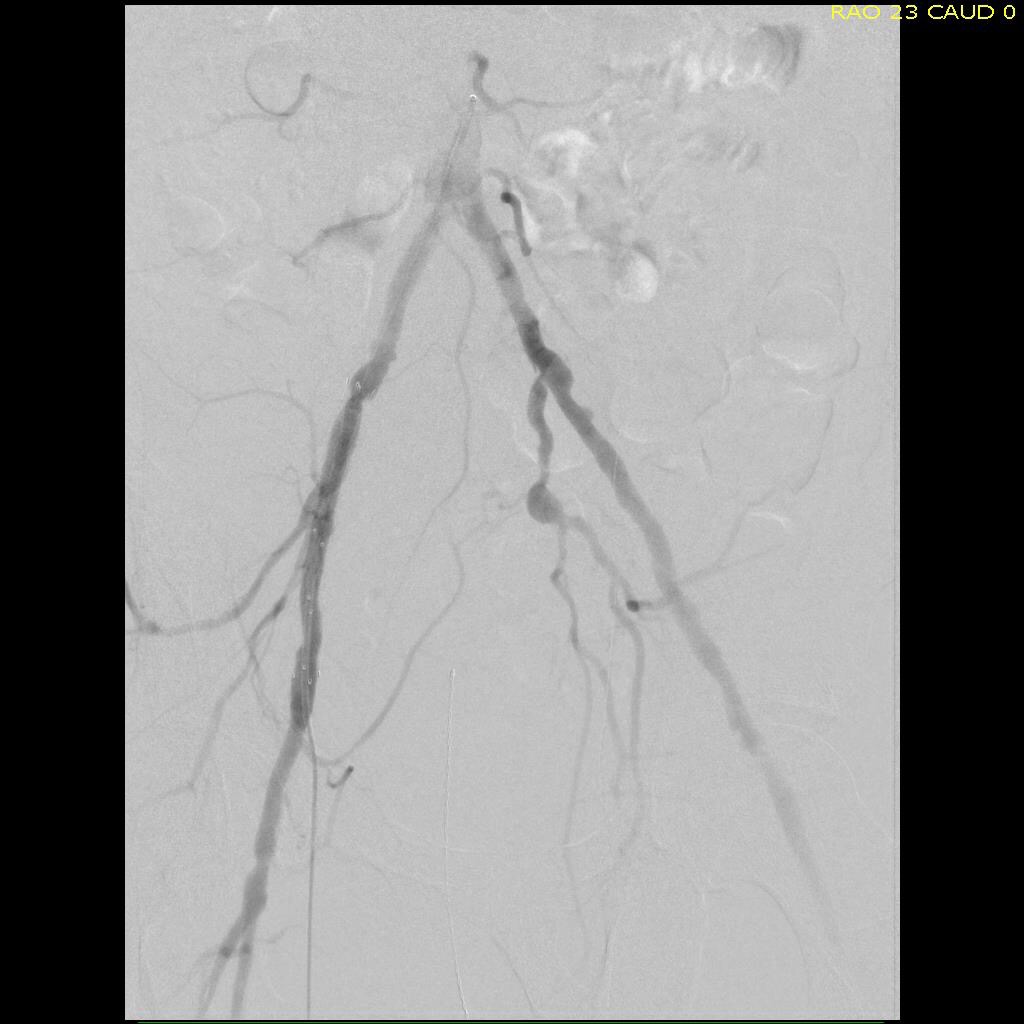

Let me show you one of the first cases I did after returning to Cleveland. I am now practicing at Fairview and Avon Hospitals, premier flagship hospitals in the Cleveland Clinic fleet, on Cleveland’s west side, and a patient arrived while I was on call with sudden onset of pain in his leg from a lack of blood flow. He had occlusive atherosclerotic plaque extending from his external iliac artery to the above knee popliteal artery causing ischemic rest pain.

I contacted LeMaitre Vascular and got in touch with your representative, L. Fisher, who promptly sent the Moll Ring Cutters I needed to perform a remote endarterectomy of the patient’s occlusive external iliac and superficial femoral artery plaque. The technical details of remote endarterectomy are have been covered in my blog (https://vascsurg.me/?s=endore), but in the end, through a 7cm incision in the groin (don’t believe the hype, this is minimally invasive), I restored his arteries to their original open condition. Shown below are the results. It was with great sadness that I heard that the LeMaitre Vascular equipment being sent were the last of the stock available in North America. The patient did very well, with the operation completed well before lunch, and is recovering rapidly from his small wound and big rescue. He gets to walk out of the hospital on two legs, but also with the surety that he avoided a major bypass operation, and avoided the short term gains of stenting from the aorta to the profunda -more peel packs and landfill items and a dubious long term durability. Hey, I even used a XenoSure patch on the common femoral.